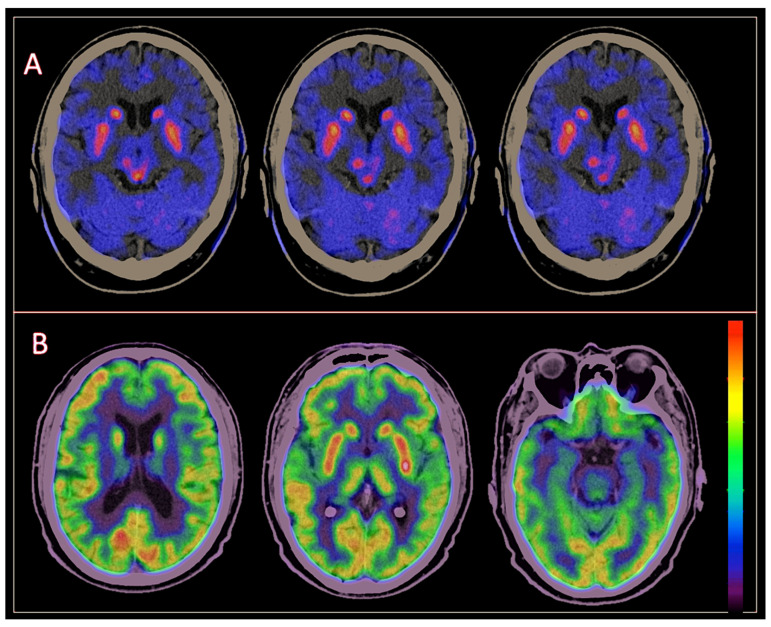

In 2021, the study conducted by Xian et al. [ref. 10] investigated the analysis of a coregistered set of dual PET/CT images with FDOPA and FDG in the differential diagnosis between PD and MSA-P, compared to healthy individuals, demonstrating the crucial value of the dual method in this aspect, which is perhaps the clinical scenario that represents the greatest diagnostic challenge. In our cohort, dual PET/CT changed the clinical diagnosis from PD to MSA-C in six patients and to MSA-P in seven patients; it also changed the clinical diagnosis from MSA-P to PD. This information offers exceptional value for better classifying these patients, with the goal of establishing a more accurate prognosis and, consequently, providing better treatment and follow-up. (Figure 2, Figure 3 and Figure 4).

When analyzing the findings of PET/CT per radiopharmaceutical, we found that, regarding FDOPA, 149 out of 150 patients presented some type of alteration in the presynaptic dopaminergic pathway, with a greater defect in the posterior third of the putamen (89% of cases); the most frequent pattern was asymmetrical in 64.7%. The only Parkinsonism that exhibited a symmetric uptake defect pattern was MSA-C; on the other hand, only one patient with a clinical diagnosis of DLB showed integrity in the presynaptic dopaminergic pathway, although the uptake pattern on FDG PET was consistent with that of the clinical diagnosis. In 2020, Stormezand and collaborators reported data that supported the findings of decreased uptake on FDOPA PET in both idiopathic PD and atypical Parkinsonisms, with predominance in the posterior third of the putamen [ref. 20].

Nurmi and Brousolle reported in different studies that PD first shows alterations in the posterior putamen, followed by the anterior putamen and caudate nuclei, involving the side contralateral to the clinically affected one [ref. 23,ref. 24]. In our cohort, all PD patients presented a presynaptic dopaminergic pathway alteration; according to the literature, up to 10–20% of clinically diagnosed PD cases have shown integrity of the presynaptic dopaminergic pathway when evaluated by PET [ref. 25]. This situation can also occur with DLB, in which a study demonstrates that integrity of the presynaptic dopaminergic pathway does not rule out the diagnosis [ref. 26]; this is similar to the example mentioned above, where the diagnosis was established by the altered pattern in cerebral glucose metabolism, highlighting the importance of dual studies when clinical suspicious is high.

It has been described that in MSA-P, the pattern of decreased uptake with the FDOPA tracer is primarily evident in the caudate nuclei and anterior putamen [ref. 27]. This information differs from our findings, where, as mentioned earlier, the posterior putamen was the most affected. In the case of CBD, the alteration of the striatal nuclei on the side opposite to the clinically affected hemibody has been described [ref. 28], similar to our findings. Normal findings have also been reported; however, in our study, we did not have any normal findings in this pathology.

In our experience, the evaluation of movement disorder cases using dual FDOPA–FDG PET/CT provides higher diagnostic accuracy than when each tracer is evaluated separately. FDOPA imaging, when abnormal, indicates dysfunction in the presynaptic dopaminergic pathway, suggesting the presence of a neurodegenerative Parkinsonism and ruling out non-neurodegenerative causes. However, FDOPA alone cannot differentiate between various neurodegenerative Parkinsonisms. On the other hand, FDG, by evaluating cerebral glucose metabolism, can differentiate between atypical Parkinsonisms based on specific metabolic patterns, but only in the context of a confirmed neurodegenerative Parkinsonism, which requires prior confirmation with FDOPA (or any other radiotracer that evaluates the dopaminergic presynaptic pathway).